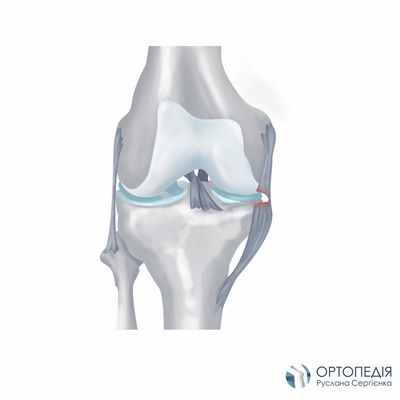

Каждый день мы делаем тысячи шагов, поднимаемся и спускаемся по лестнице, приседаем, занимаемся спортом. Выполнять эти движения свободно и без боли дает возможность особенное строение коленного сустава, в том числе наличие связок. Коленные связки (всего их четыре: две крестообразные и две наружные) обеспечивают правильное положение сустава и его стабильность. Передняя и задняя крестовидные связки удерживают колено при движении вперед-назад. При движениях в стороны сустав фиксируют внутренняя и внешняя боковые связки (медиальная и латеральная). Сами по себе эти структуры очень прочные, однако физические перегрузки, травмы и заболевания суставов могут спровоцировать повреждение связок колена.

АНАТОМИЯ

Связки представляют собой прочные структуры из соединительной ткани, которые соединяют кости друг с другом. Коленный сустав укреплен двумя коллатеральными (боковыми) связками, которые предотвращают избыточное отведение и приведение голени. Медиальная коллатеральная связка находится на внутренней поверхности коленного сустава, то есть на стороне, обращенной к другому коленному суставу. Латеральная коллатеральная связка располагается на наружной стороне коленного сустава. Чрезмерное растяжение этих связок в результате травмы может закончиться их разрывом. Линия разрыва может находиться в любом месте связки, как в центре связки, так и у места прикрепления ее к костям. При значительной травме может происходить сочетанное повреждение коллатеральных и внутрисуставных связок коленного сустава.

Наиболее часто в клинической практике отмечается сочетание разрыва медиальной коллатеральной и передней крестообразной связок. Передняя крестообразная связка расположена внутри коленного сустава, в его центральной части, а ее функция заключается в ограничении движения большеберцовой кости в переднем направлении относительно бедренной. Частота разрыва медиальной коллатеральной связки выше, чем латеральной коллатеральной, однако вероятность развития нестабильности коленного сустава выше при последнем виде травматического повреждения. Одна из причин высокой частоты нестабильности сустава при разрыве латеральной коллатеральной связки состоит в том, что медиальная часть большеберцового плато имеет более глубокое углубление. Напротив, со стороны латеральной коллатеральной связки большеберцовое плато имеет плоскую поверхность, в связи с чем амплитуда движения костей в этом отделе сустава выше.